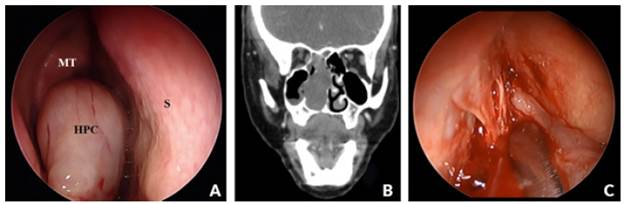

The patient underwent a 3-year follow-up, during which time she remained free of symptoms and showed no signs of local or meta-static recurrence on objective examination and CT-PS imaging (Figure 3).

(A) After removing hemangiopericytoma; (B) Endoscopic examination without evidence of local recurrence (3-year follow-up). MT - Middle Turbinate; S- Nasal Septum; (C) CT paranasal sinuses in soft tissue window (coronal) - 3-year follow-up.

Figure 3: (A) After removing hemangiopericytoma; (B) Endoscopic examination without evidence of local recurrence (3-year follow-up). MT - Middle Turbinate; S- Nasal Septum; (C) CT paranasal sinuses in soft tissue window (coronal) - 3-year follow-up.